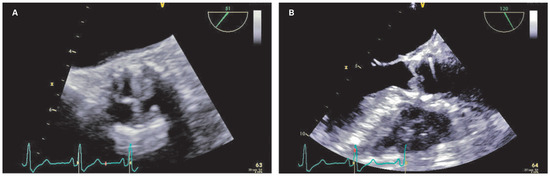

Case report